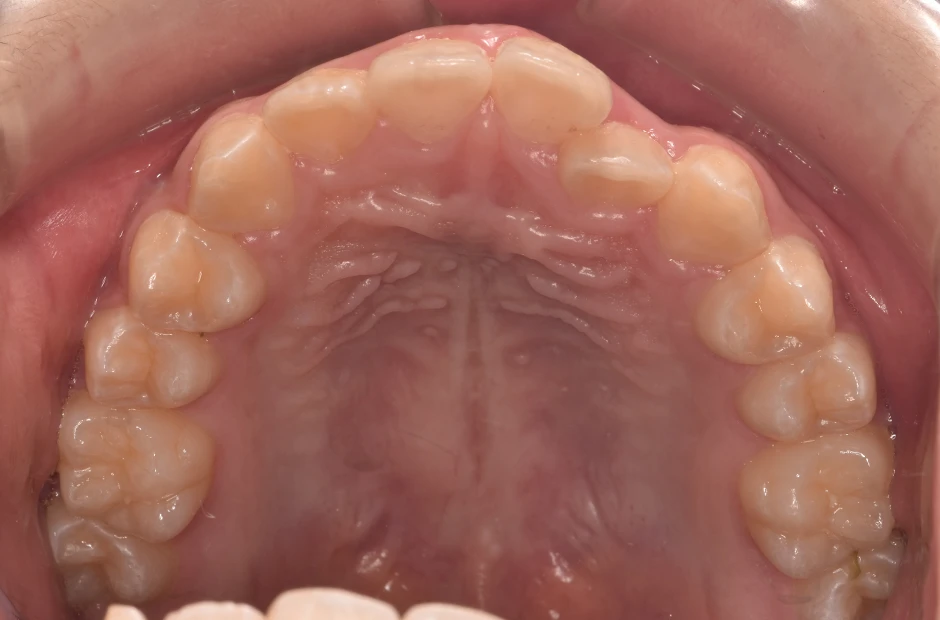

治療症例

ブラケット矯正

前歯部反対咬合

| 診断名・主訴 | 前歯部反対咬合 |

|---|---|

| 年齢・性別 | 14歳・男性 |

| 治療期間・回数 | 1年2か月 |

| 治療に用いた主な装置 | ブラケット矯正 |

| 抜歯部位 | なし |

| 治療費 | 60万円(税抜) |

| リスク・副作用 | 装置による違和感・疼痛・歯肉退縮・歯根吸収・虫歯のリスクなど |

治療前